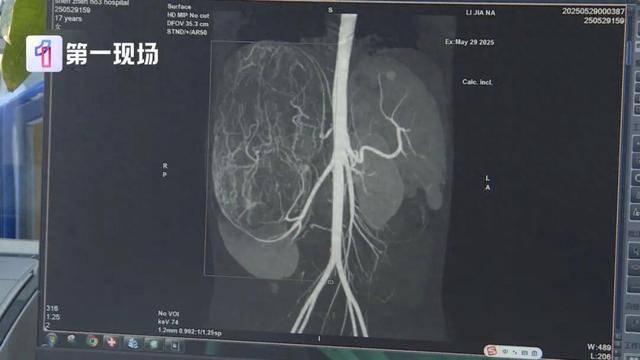

婷婷的肚子里

竟然长了一个巨大的肿瘤

直径长达27厘米

等到了当地医院一检查,CT结果显示,她的右肾有恶性肿瘤伴肝转移可能,家长就立即带着孩子来到深圳求医。

肿瘤已经到了肚脐的下缘,就是后腹直肌外侧,这种情况需安全地把肿瘤切除,不要把肿瘤搞破,是我们首先要考虑的问题。

切除的肿瘤将近5斤重

直径达27厘米

肿瘤切出来后,我们测量了大小有27公分,重量有2.435公斤,非常非常的大。